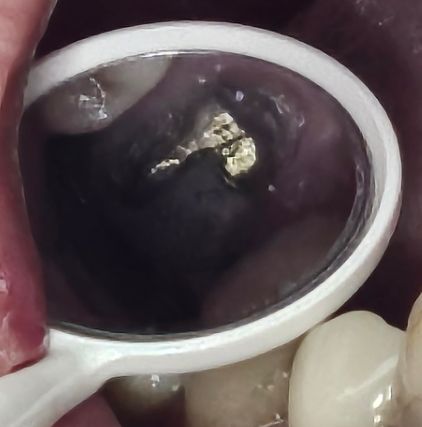

根幹3本中1本の歯根破折、フィステルにより、痛みやぐらつきはありませんが、先日、右上6番の分割抜歯を行いました。

メタルコア上のジルコニアクラウンで、冠を外し無事に分割抜歯の処置を終えました。

メタルコアの除去が難しいので、このまま使いましょうと言われ、なぜか隣の部位まで大きく削られ、コア柱がTバッグのように剃刀の刃ほどに薄くなっています。

通常、悪い部分だけ取るならL字形に太く柱を残すはずです。

なぜ、このような削り方をされたか判りません。

コアを肉盛りする事は可能なのでしょうか?

5番6番のブリッジとの事ですが強度的にとても不安です。

L字はブラッシング出来ないので、本当は写真のように真っ直ぐになるように当院では歯周病の手術を行なってからクラウン(ブリッジ)にしています。